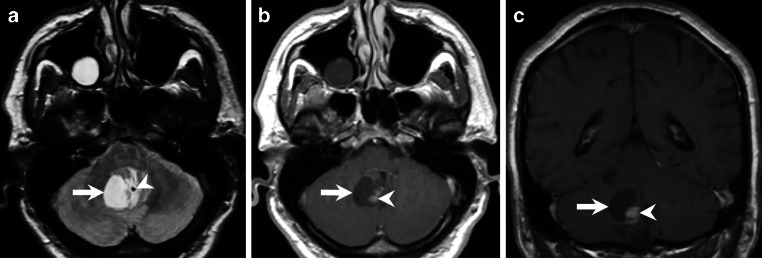

Abstract Image